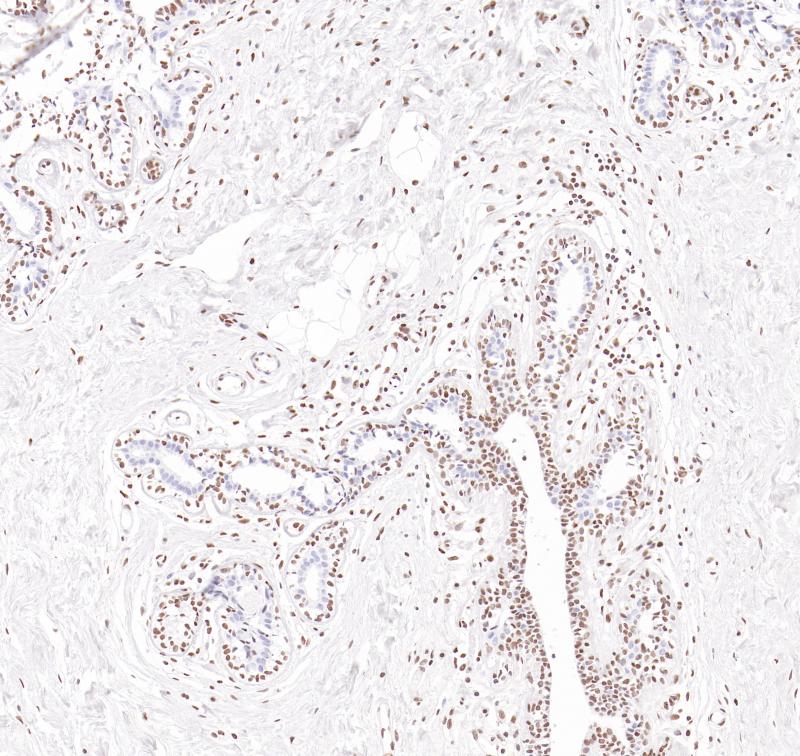

肾MDR-1(BP6260)染色

MDR-1

重组兔单克隆抗体

多药耐药蛋白1(MDR-1,又称P-糖蛋白),是由MDR基因所编码的一种膜型糖蛋白,有ATP依赖性跨膜转运活性,可将药物转运至细胞外,使细胞获得耐药性。研究表明,MDR1可以减少癌细胞中的药物积累,从而导致耐药性的产生。MDR-1主要用于各种恶性肿瘤(如肝癌、乳腺癌、胃肠道癌)的研究。

目录号

BX50283

克隆号

BP6260

阳性对照

肾

亚细胞定位

细胞膜

组织类型

FFPE

修复方式

HIER

稀释比

1:100-1:200

规格

100μl/vial, 1ml/vial

用途

RUO